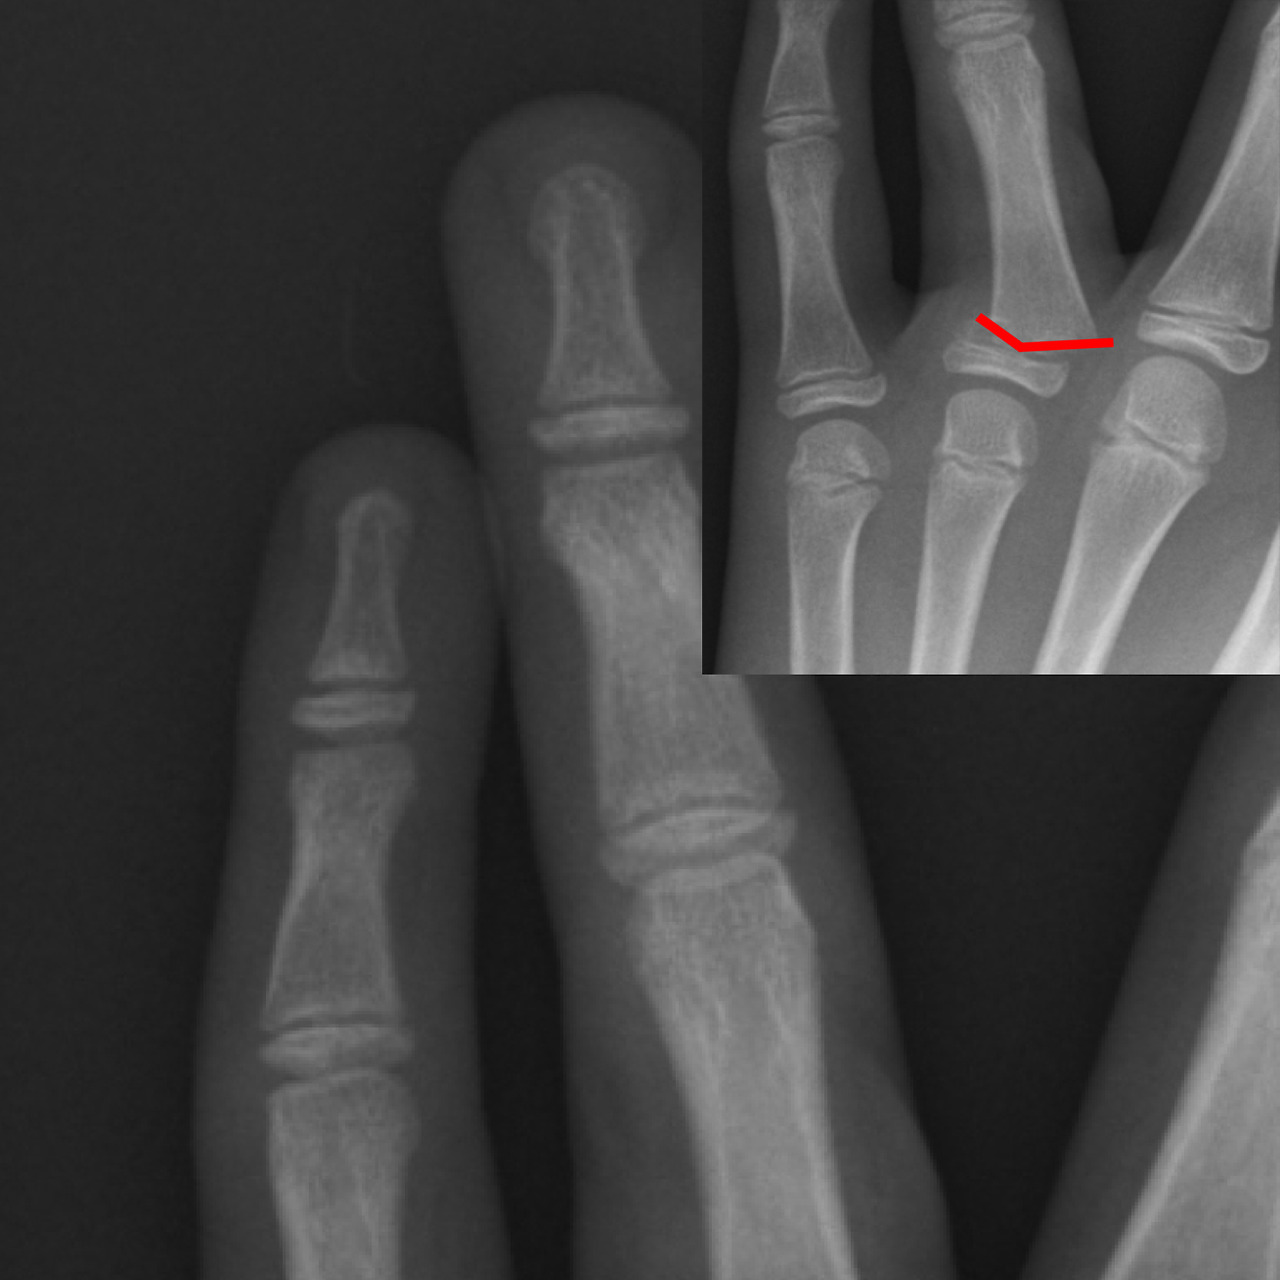

반대로 깁스 또는 보다 강한 고정이 필요한 경우는 다음과 같습니다.

- 골절로 인해 뼈가 어긋난 경우

- 관절면이 손상된 경우

- 여러 조각으로 부러진 분쇄 골절

- 스플린트 착용 후에도 통증과 불안정성이 지속되는 경우

즉, 손가락 뼈에 금이 갔다는 진단만으로 깁스를 결정하기보다는, 골절의 형태와 안정성, 기능 손상 여부를 종합적으로 고려해야 합니다. 과도한 고정은 오히려 관절 강직을 유발할 수 있으므로, 최소한의 고정으로 최대의 회복을 목표로 하는 것이 치료의 핵심입니다.